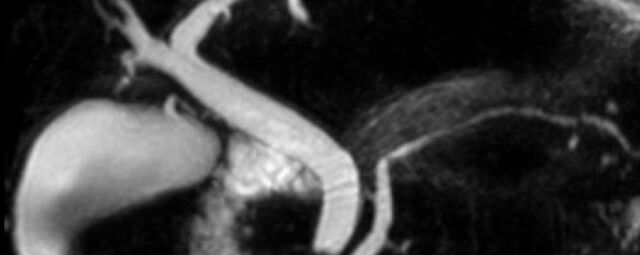

MRT - Herzens

Diese Untersuchung führen wir ausschließlich an unserem Standort in Leipzig am Diakonissenkrankenhaus durch. Bitte nehmen Sie zur Vereinbarung eines Termins telefonischen Kontakt mit uns auf: 0341 3937-3000 oder schreiben Sie uns eine E-Mail an:

MRT Thorax

MR-Angiographie zur Erfassung und Verlaufskontrolle von Aneurysmen der Aorta thorakalis und ihrer Gefäßabgänge